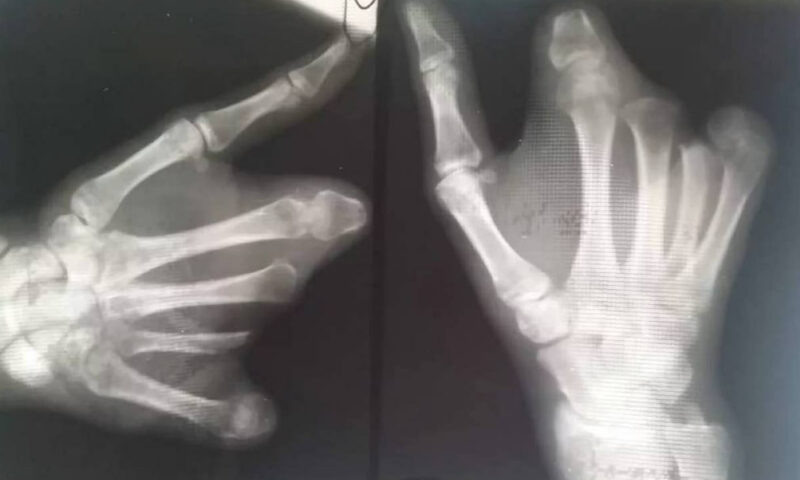

Фото t.me/tipichkras

Как писал интернет-портал «Кубань 24», пострадавшего мальчика госпитализировали, у ребенка диагностировали контузию левого глаза, множественные ссадины на лице и рваную рану левой кисти.